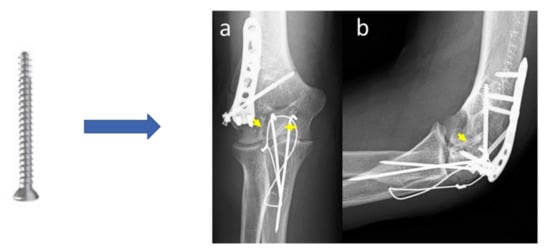

- Aktan, C.; Ertan, M.B.; Turan, A.; Kose, O. Fixation of Small Osteochondral Fragments in a Comminuted Distal Humerus Fracture with Magnesium Bioabsorbable Screws: A Case Report. Cureus 2018, 10, e3752. [Google Scholar] [CrossRef]

- Lam, W.-H.; Tso, C.-Y.; Tang, N.; Cheung, W.-H.; Qin, L.; Wong, R.M.-Y. Biodegradable Magnesium Screws in Elbow Fracture Fixation: Clinical Case Series. J. Orthop. Trauma Rehabil. 2021. [Google Scholar] [CrossRef]

| Elbow fracture | 2.7 mm diameter screws | Mg-Y-RE-Zr (MAGNEZIX®, Syntellix AG) | Human female 48 years old (2020) | [24] |

| Humeral fracture (elbow) | 1 | Excellent | 4 months | None | [21] |

| 1 | Excellent | 24 months | None | [145] | |